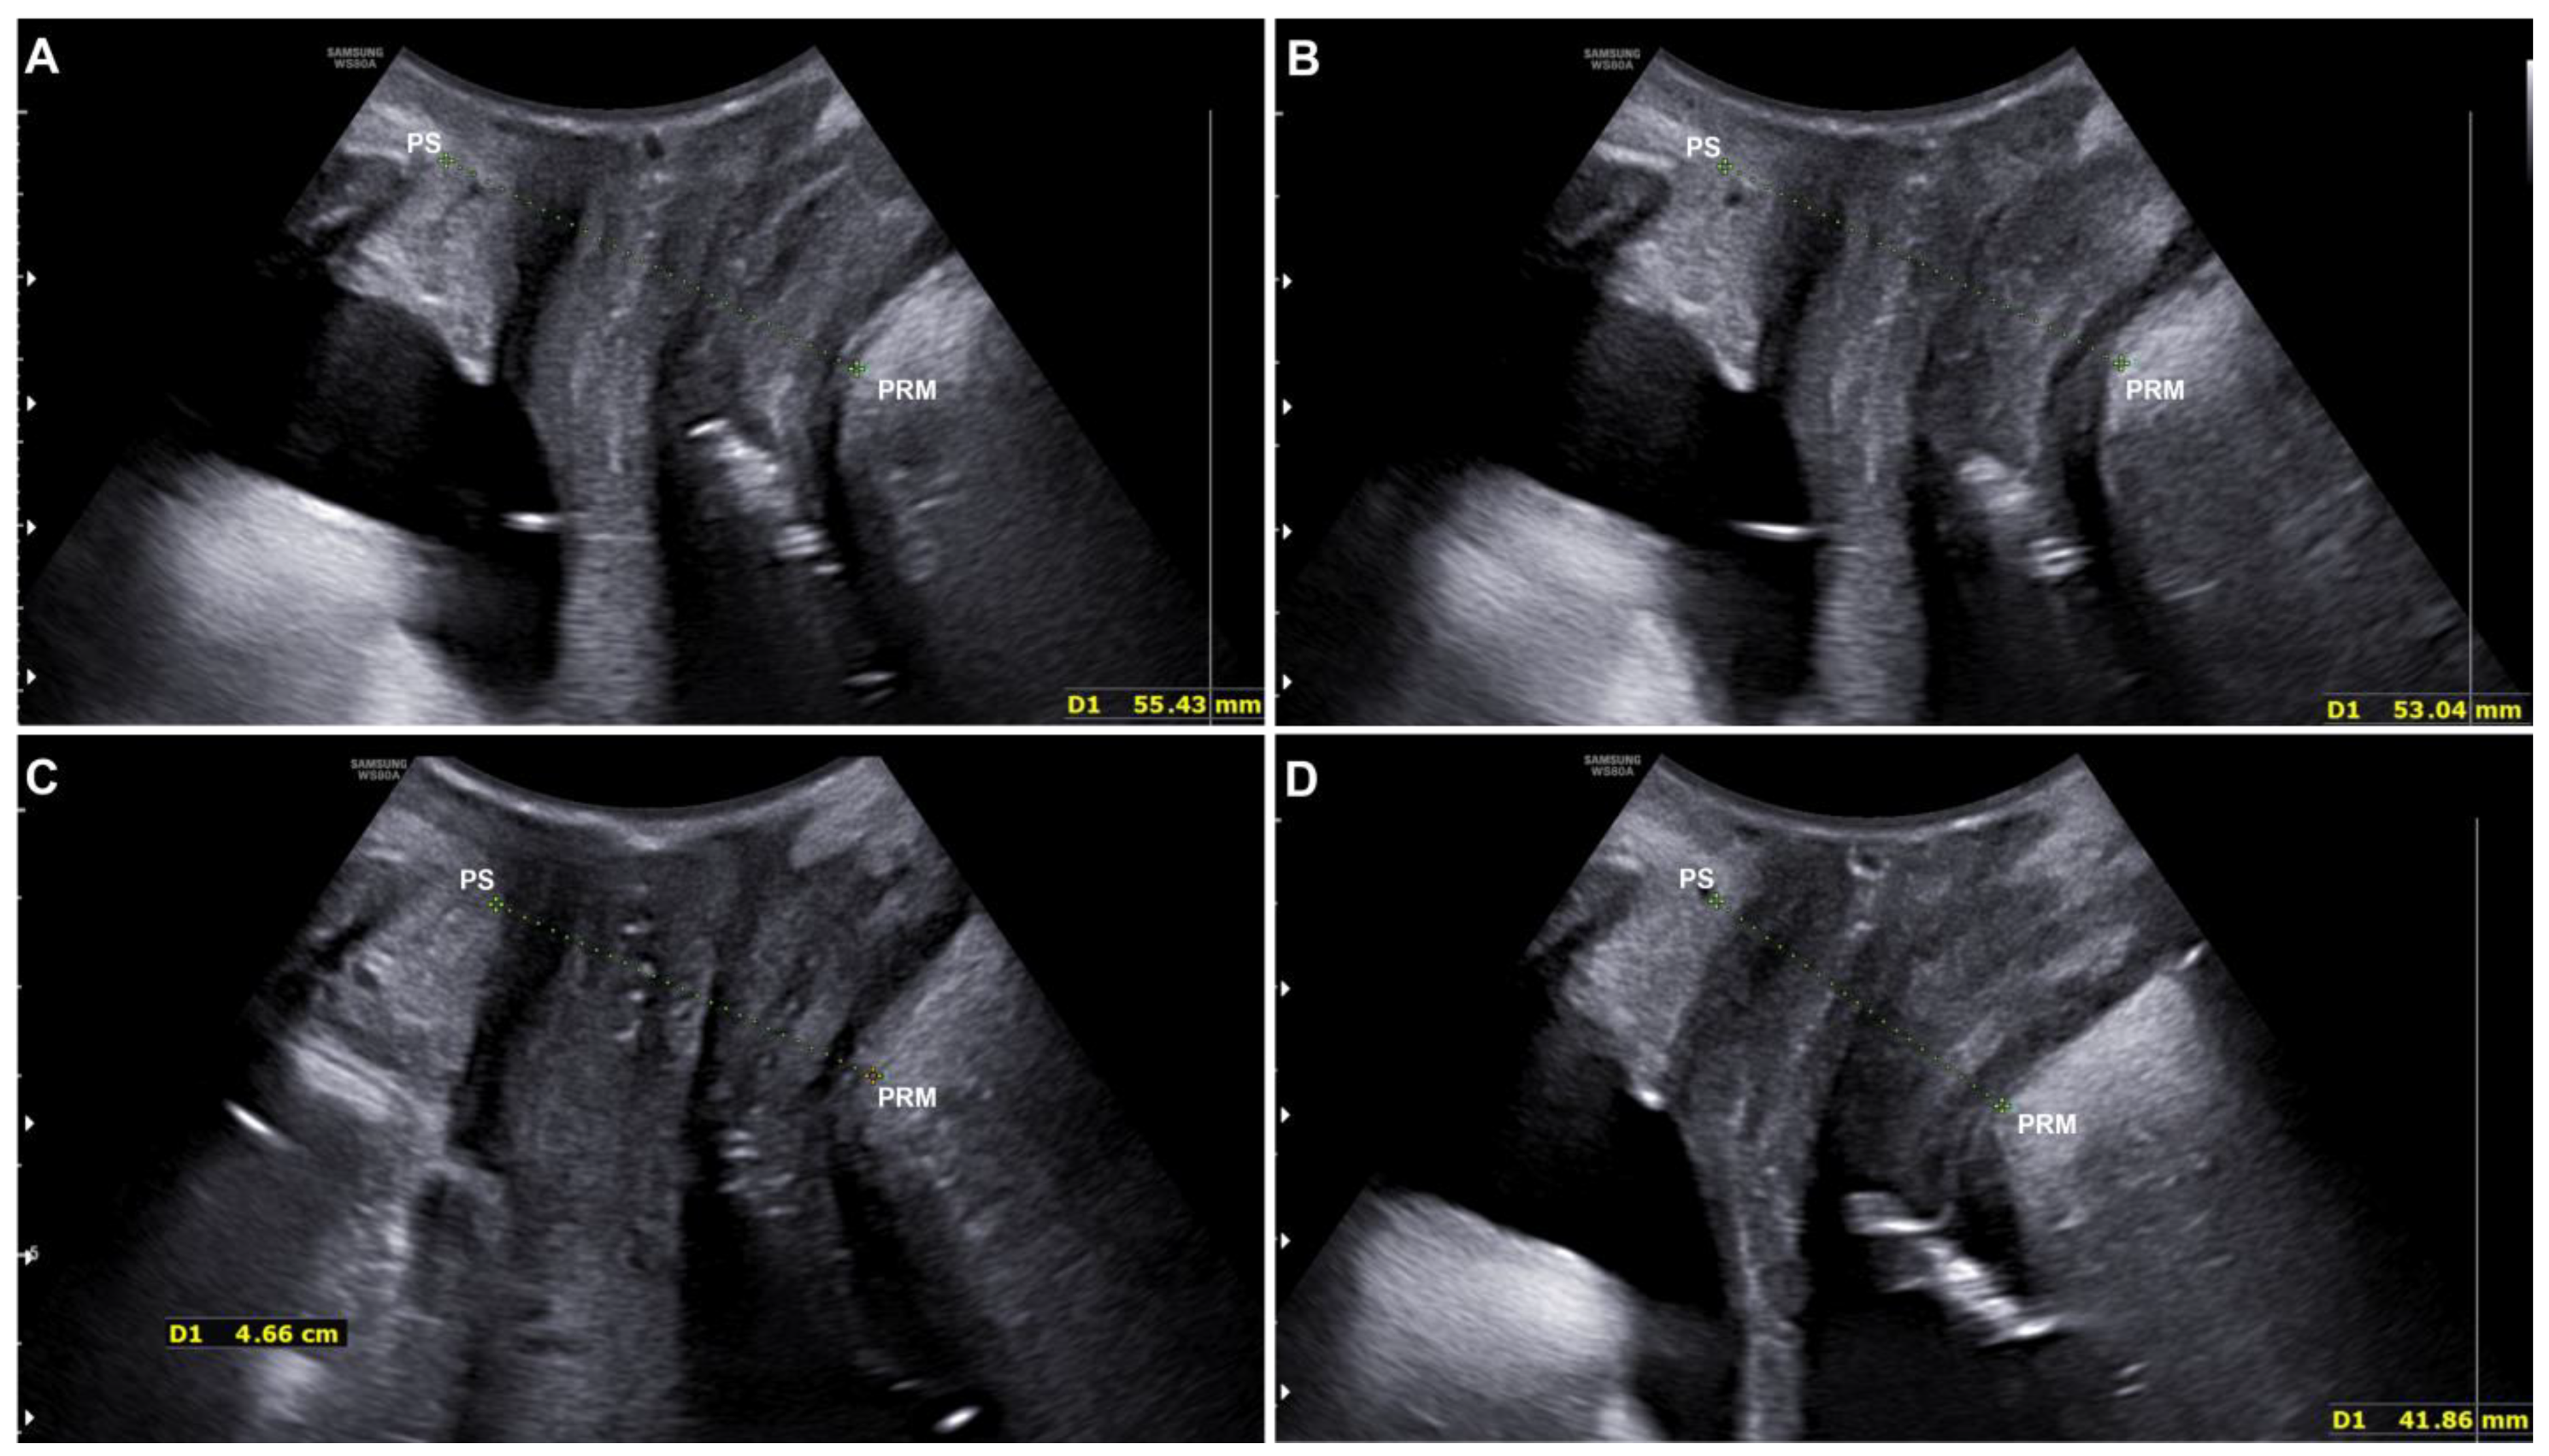

Pre- and post-treatment improvements were compared using the distance between the hyperechogenic posterior surface of the pubic symphysis and the hyperechogenic medial–anterior border of the puborectalis muscle of the levator ani.

The results showed a statistically significant (p < 0.001) distance reduction, both at rest (from 56.57 ± 6.52 mm to 54.32 ± 6.38 mm) and in a stress (contraction) condition (from 47.9 ± 4.86 mm to 44.80 ± 5.07 mm) (see Figure 3 and Table 3).

The distance between the inferior border of the pubic symphysis and the medial border of the levator ani (puborectalis muscle) was used to compare pre- and post-treatment improvements. PS = pubic symphysis; PRM = puborectalis muscle.

Figure 3. Ultrasound evaluation of a patient at rest before (A) and after (B) the treatment with electromagnetic stimulation. The ultrasound evaluation performed on the same patient under stress/contraction condition before (C) and after (D) the treatment with electromagnetic stimulation. The green lines represent the distance between the PS (pubic symphysis) and the PRM (puborectalis muscle).